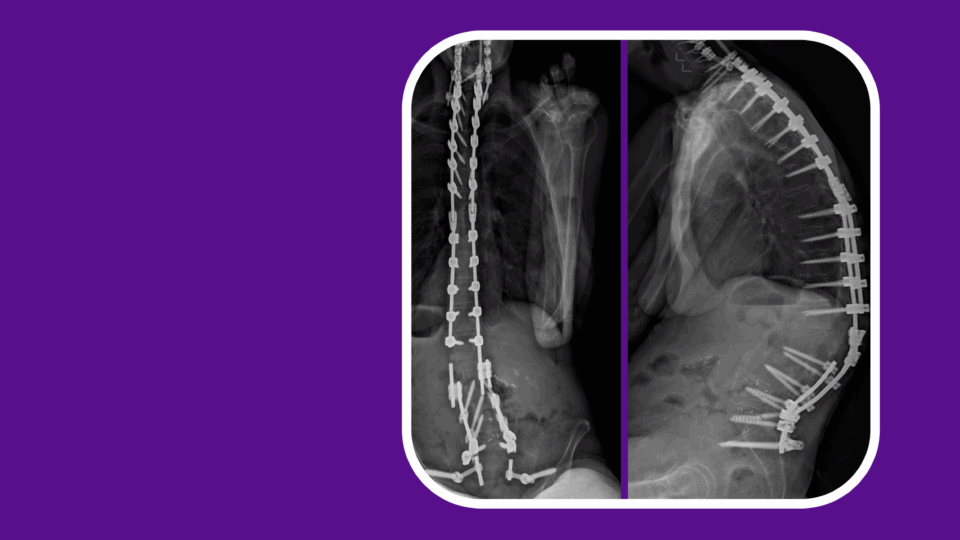

Techniques: How I Do It: VCR/3 Column Osteotomies

Session: SYM13B: Pediatric Spinal Deformity

NYU Langone Presenter: Darryl Lau, MD